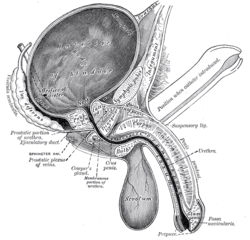

Vesiculae seminales and ampullae of ductus deferentes, front view. Vertical section of bladder, penis, and urethra.

Vertical section of bladder, penis, and urethra. Dissection of prostate showing prostatic urethra.